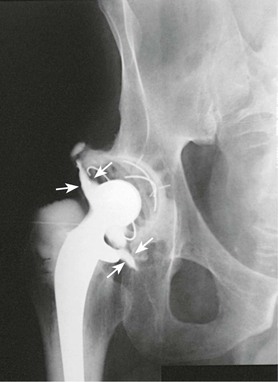

Hip arthrography is most often performed on children in a surgery suite by an orthopedic surgeon. Arthrography is used to evaluate lateral femoral head displacement and after closed reduction to ensure that there is no folding or impingement of soft tissues (see Fig. 12-2, pretreatment) (Figs. 12-14 and 12-15, post-treatment). In adults, the primary use of hip arthrography is to detect a loose hip prosthesis or to confirm the presence of infection. The cement used to fasten hip prosthesis components has barium sulfate added to make the cement and the cement-bone interface radiographically visible (Fig. 12-16). Although the addition of barium sulfate to cement is helpful in confirming proper seating of the prosthesis, it makes evaluation of the same joint by arthrography difficult.

Because cement and contrast material produce the same approximate radiographic brightness, a subtraction technique is recommended—either photographic subtraction, as shown in Figs. 12-17 and 12-18, or digital subtraction, as shown in Figs. 12-19 and 12-20 (see Chapter 23). A common puncture site for hip arthrography is